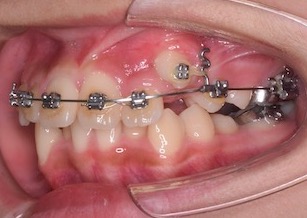

Before Ⅳの写真は、口腔外科にて埋伏していた左側上顎犬歯を歯肉開窓し、ブラケットを装着した時の写真です。

③左側上顎埋伏歯へのアプローチとして以下の手順にて矯正治療を行いました。

A:上顎歯列にマルチブラケット装置を装着する。

B:ワイヤーの交換を順次行い、歯列のレベリングとスタビライズを行う。埋伏歯のための十分なスペースを確保する。

C: 準備が整ったところで口腔外科にて埋伏歯部の歯肉開窓(切開)を行っていただく。→埋伏歯の表面に矯正医がブラケットを装着する。

D:スタビライズされた歯を固定源として、適切なフォースとベクトルで埋伏歯を牽引する。

After Ⅰの写真は、左側上顎犬歯を牽引・移動中の口腔内写真です。